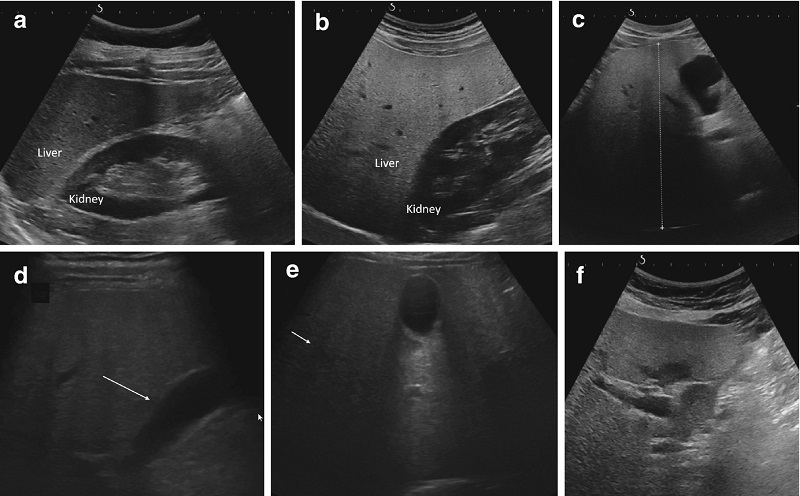

Siêu âm gan là kỹ thuật chẩn đoán hình ảnh được sử dụng rộng rãi tại các bệnh viện trong và ngoài nước. Với máy siêu âm, bác sĩ chuyên khoa đánh giá các cấu trúc của gan như nhu mô gan, mạch máu gan, đường dẫn mật trong và ngoài gan, túi mật… Trong quá trình siêu âm gan, bác sĩ còn quan sát được các cơ quan khác trong khoang bụng như thận, tụy, lách... và các mạch máu của gan.

Nhờ siêu âm, các bác sĩ có thể phát hiện tổn thương gan và bệnh của các cơ quan khác, bệnh gan liên quan, e.g. ung thư gan, xơ gan, gan nhiễm mỡ hay sỏi mật, polyp đường mật, ung thư đường mật, tắc mạch gan… Từ đó có thể xử lý kịp thời. chẩn đoán và hướng dẫn điều trị hiệu quả các bệnh liên quan đến bệnh.

Siêu âm gan có thể đo độ cứng của nhu mô gan và suy ra mức độ xơ hóa của gan. Nó giúp bác sĩ quyết định có điều trị hay không và tiên lượng, theo dõi các biến chứng của xơ gan.

Ngày nay, khi tình trạng béo phì, lười vận động, lười vận động hay uống nhiều rượu bia thì tỷ lệ người mắc gan nhiễm mỡ cũng cao hơn. Bệnh nhân gan nhiễm mỡ có nguy cơ phát triển bệnh gan nhiễm mỡ, xơ gan và ung thư gan. Nếu bệnh nhân bị gan nhiễm mỡ, kết quả siêu âm cho thấy gan tăng phản âm nhiều hơn so với gan bình thường, hoặc hình ảnh siêu âm gan xuất hiện những mảng hồi âm dày rải rác hoặc tập trung tại các vùng, ở ranh giới của các cấu trúc.

Kiểm tra siêu âm gan có thể cho thấy gan bị viêm hoặc tổn thương. Lúc này có thể thấy gan sưng to, kích thước gan tăng lên, nhu mô gan không có sự thay đổi rõ rệt nhưng gan đã bị tổn thương. Một số thiết bị siêu âm tiên tiến có thể đo độ nhớt của nhu mô gan bằng siêu âm gan, độ nhớt càng cao thì nhu mô gan càng bị viêm.

Ung thư đường mật được coi là một trong những loại khối u có tiên lượng dè dặt. Các khối u này thường làm hẹp các phần của ống mật, tiến triển dần dần làm cho mật bị ngưng trệ, làm cho ống mật bị giãn rộng ra trước khi bị hẹp. Hình ảnh này rất dễ tìm thấy khi siêu âm gan.